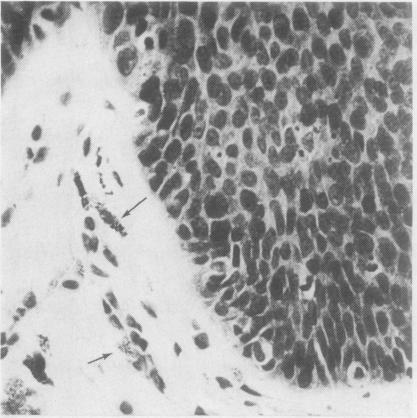

The pathological, cytological, and clinical features of vulvar intraepithelial neoplasia (VIN) are described. The rate of progression of VIN III to an invasive carcinoma is very low and spontaneous regression can occur. These features prevent the drawing of a direct analogy between vulvar and cervical intraepithelial neoplasia. The concept of microinvasive carcinoma of the vulva is discussed, and it is concluded that no satisfactory definition of this entity has been achieved.

本文描述了外阴上皮内瘤变(VIN)的病理、细胞学及临床特征。VIN III进展为浸润性癌的发生率很低,且可发生自发消退。这些特征使得外阴上皮内瘤变与宫颈上皮内瘤变无法直接进行类比。文中对外阴微浸润癌的概念进行了讨论,得出的结论是尚未对该实体达成令人满意的定义。